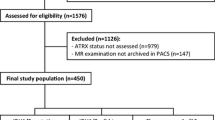

A total of 111 LrGG patients (76 mutated IDH and 35 wild-type IDH) were enrolled, divided into a training set (n = 78) and a validation set (n = 33) for predicting IDH mutation. IDH + LrGG patients were further stratified into the ATRX − (n = 38) and ATRX + (n = 38) subtypes. A total of 250 radiomics features were extracted from the region of interest of each tumor, including that from T2 fluid-attenuated inversion recovery (T2 FLAIR), contrast-enhanced T1 WI, ASL-derived cerebral blood flow (CBF), DWI-derived ADC, and exponential ADC (eADC). A radiomics signature was selected using the Elastic Net regression model, and a radiomics nomogram was finally constructed using the age, gender information, and above features.